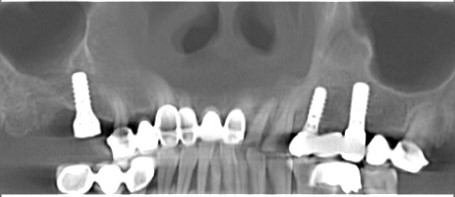

第一步:数据采集(口扫或仓扫+CBCT

第六步:最终修复